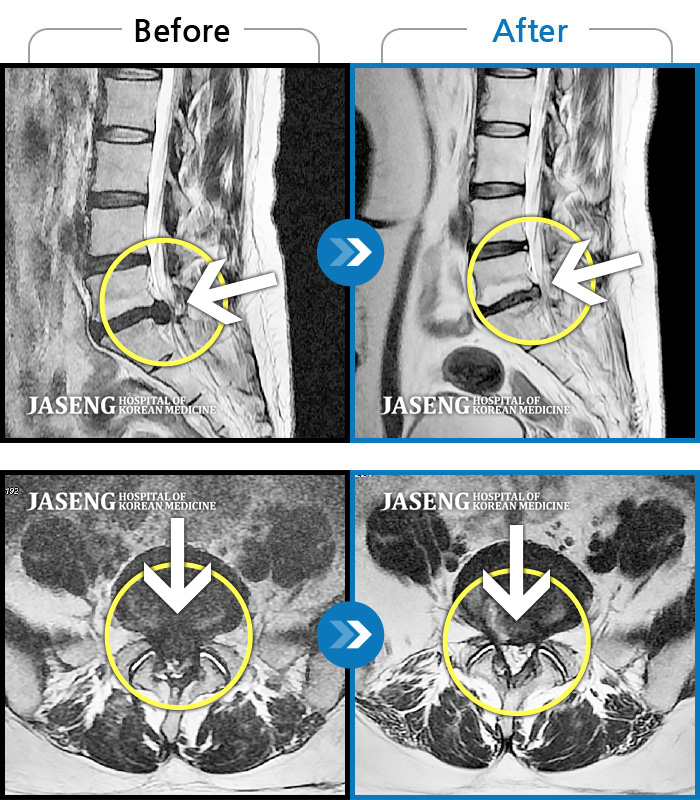

MRI ũ ʸ Ȯϼ.

[ؿ] 24.10.10~25.04.23